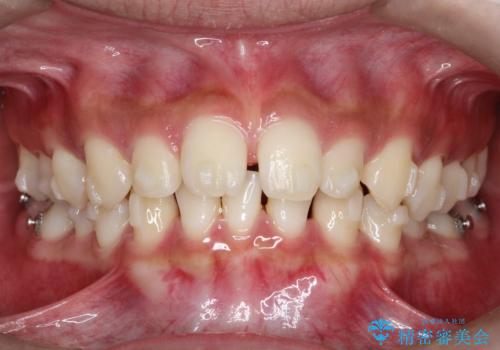

【インビザライン】空隙歯列の矯正

- 前歯の隙間を主訴に来院されました。

なるべく目立たない治療を希望されましたので、インビザラインにて治療を行なっております。

単純に前歯の隙間の閉鎖をしてしまうと、前歯に早期接触が生まれ、臼歯が噛まなくなってしまいます。適切な治療計画を立てることで、噛み合わせも良好な結果を得ることができました。